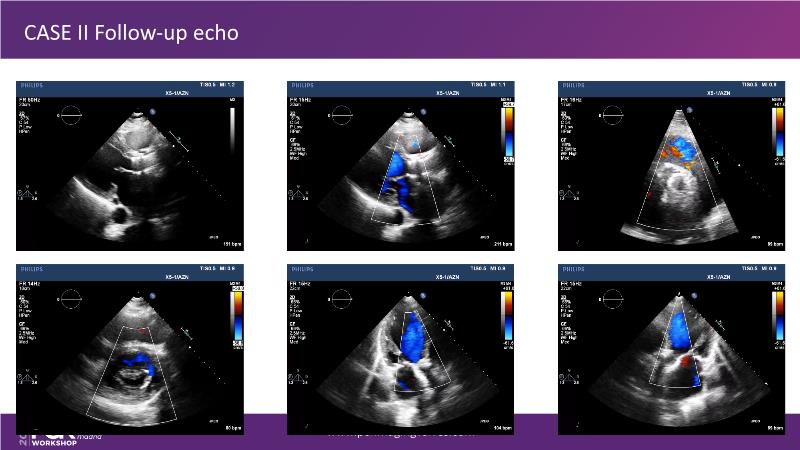

Explore cutting-edge transcatheter valve interventions for mitral and aortic valve disorders, including valve-in-valve procedures and management strategies for paravalvular leakages, and learn about diagnosing and treating mitral annular calcification and transcatheter options in infective endocarditis.